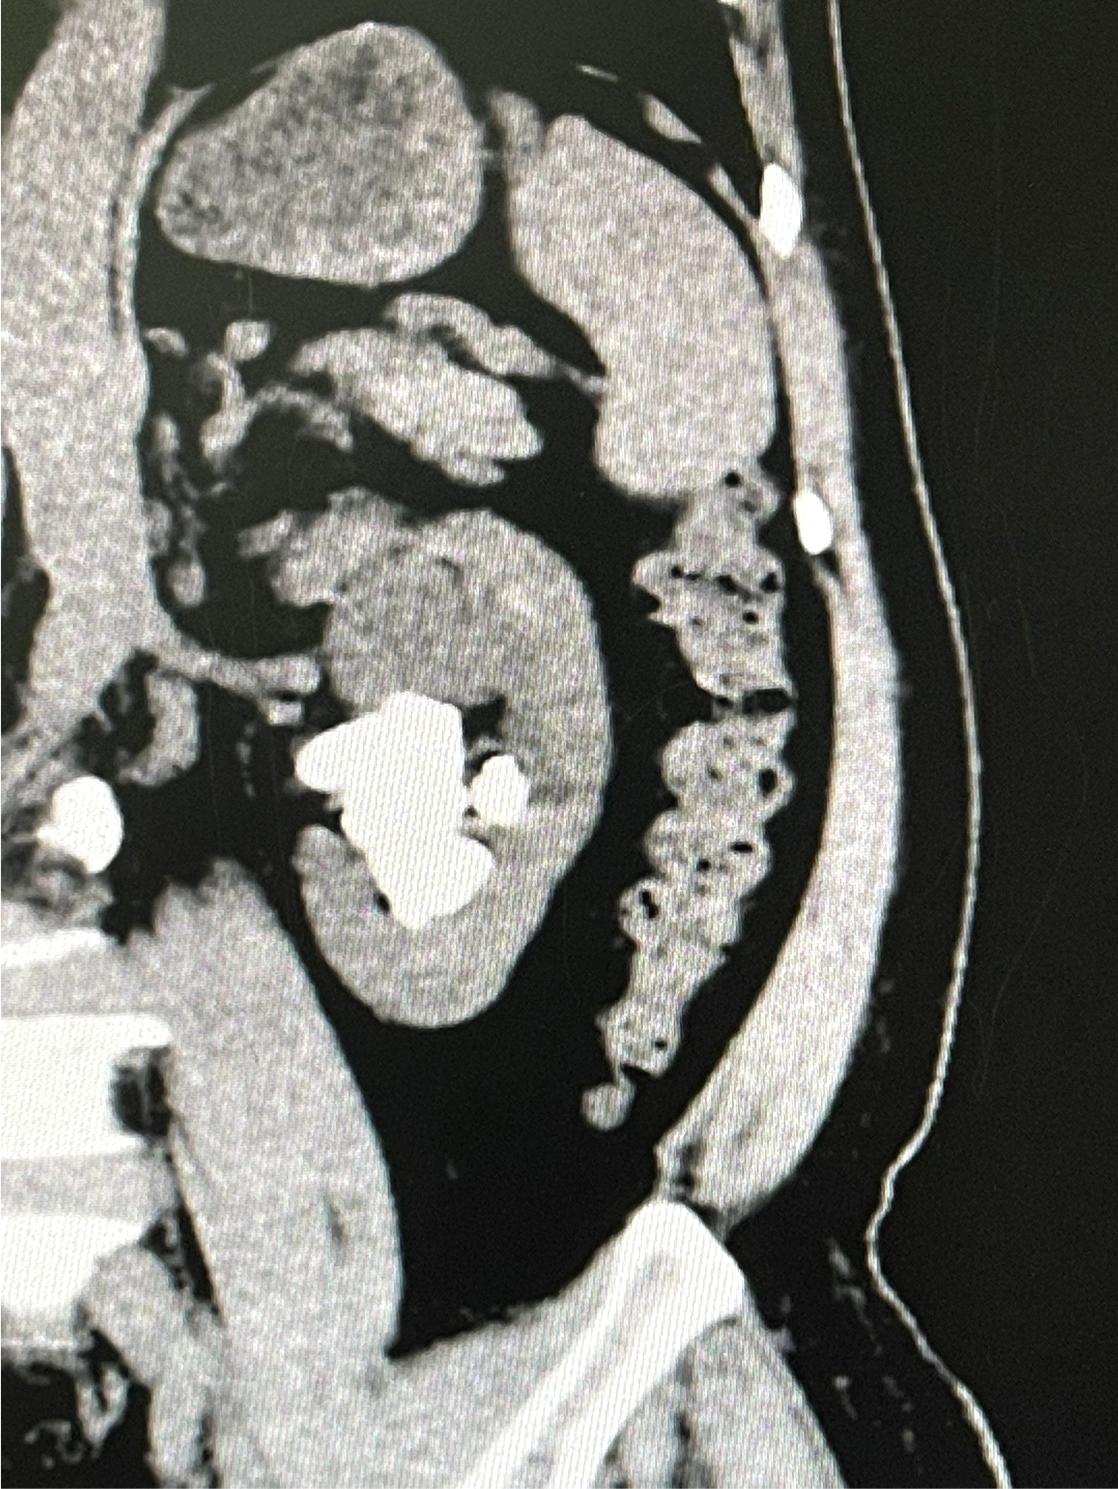

钦州宝顺医院副主任医师、泌尿外科专家、钦州宝顺医院副院长王宗绫 结石、前列腺、肿瘤一直是困扰男性泌尿系统健康的三大顽疾。作为医学技术人员,王宗绫以强烈的事业心和高度的责任感,视事业如生命,把破解泌尿外科难题当作一生的追求。自大学毕业从医20余年以来,日复一日,年复一年,他一直专注于泌尿外科的研究,不断努力提高自己的医术诊治水平,始终用真诚与爱心做一名病人满意、群众欢迎的好医生。 王宗绫认为,医生的职责就是为病人治好病和服务好病人。想要做一名好医生,为病人减轻痛苦、获得病人的认可,必须要有过硬的技术本领。为了充实和提高自己的专业理论水平和临床诊治能力,王宗绫始终将攻克泌尿外科难题与为群众提供精湛技术服务紧密结合起来,以解决复杂疑难泌尿系统疾病为己任。他远赴南方医科大学和广州医科大学进修1年,师从中国著名泌尿外科刘春晓和李逊教授学习先进的泌尿外科诊治技术以及尿路结石微创手术。平时不管工作再忙,他都要挤出时间学习专研专业理论或者了解国内外最新、最前沿的诊治技术发展情况。每遇到疑难病例、复杂手术,他常常要仔细查阅相关资料,反复推敲。

医心向党,初心如磐。王宗绫二十余年的心血都用在微创和超微创手术破解泌尿顽疾。他只是民营医院普通医生,给患治好病就是最高荣誉。(通讯员:黄孟林) |